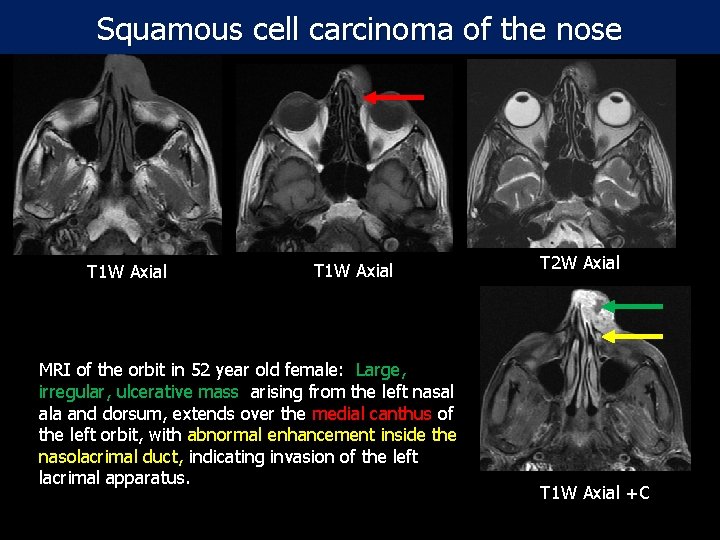

Squamous cell carcinoma of the nose T 1 W Axial MRI of the orbit in 52 year old female: Large, irregular, ulcerative mass arising from the left nasal ala and dorsum, extends over the medial canthus of the left orbit, with abnormal enhancement inside the nasolacrimal duct, indicating invasion of the left lacrimal apparatus. T 2 W Axial T 1 W Axial +C